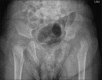

Cutis laxa is a heterogeneous group of diseases, with loose, wrinkled skin folds and hyperelasticity of the skin. There are overlapping of clinical features of the group of syndrome associated with cutis laxa, including congenital cutis laxa, wrinkly skin syndrome and gerodermia osteodysplastica. All these conditions present a challenge to the clinician. Thus, molecular diagnosis is the only way to resolve these phenotypically similar conditions. We hereby describe two Indian patients with wrinkled skin and mild craniofacial dysmorphic features who had molecular confirmation of autosomal recessive cutis laxa.